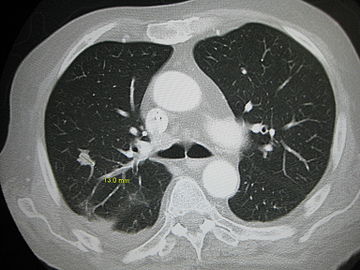

Pulmonary metastases shown on Chest X-Ray